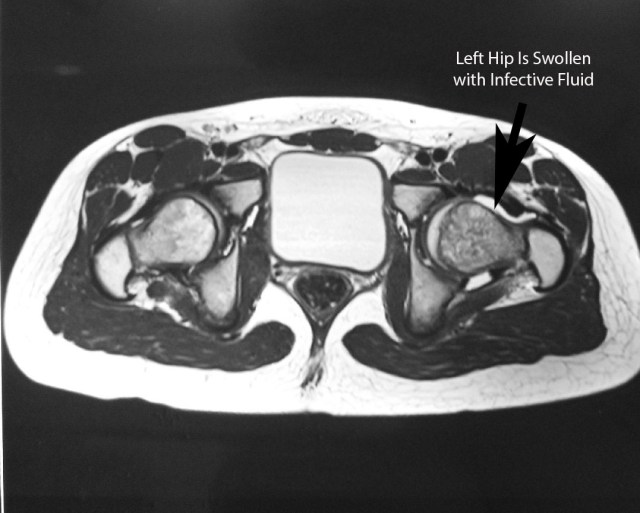

An ultrasound scan or an MRI scan of the hip joint can be done.

Surgical Treatment